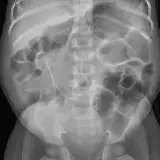

Abdominal Radiographs